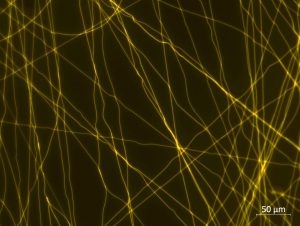

TÍTULO DE LA IMAGEN: Un rayo de sol de esperanza

AUTOR: Pedro Valentín Badía Hernández

TEXTO ARTÍSTICO-DIVULGATIVO

El cáncer se mantiene como una de las primeras causas de muerte a nivel mundial, desarrollar nuevos tratamientos suponen una de las vías de investigación más relevantes. Los «nanobiomateriales», como las nanofibras mostradas en la imagen, pueden ser una nueva plataforma de administración de fármacos antitumorales. Un rayo de sol de esperanza para todas aquellas personas que, directa o indirectamente, han sufrido por esta enfermedad.